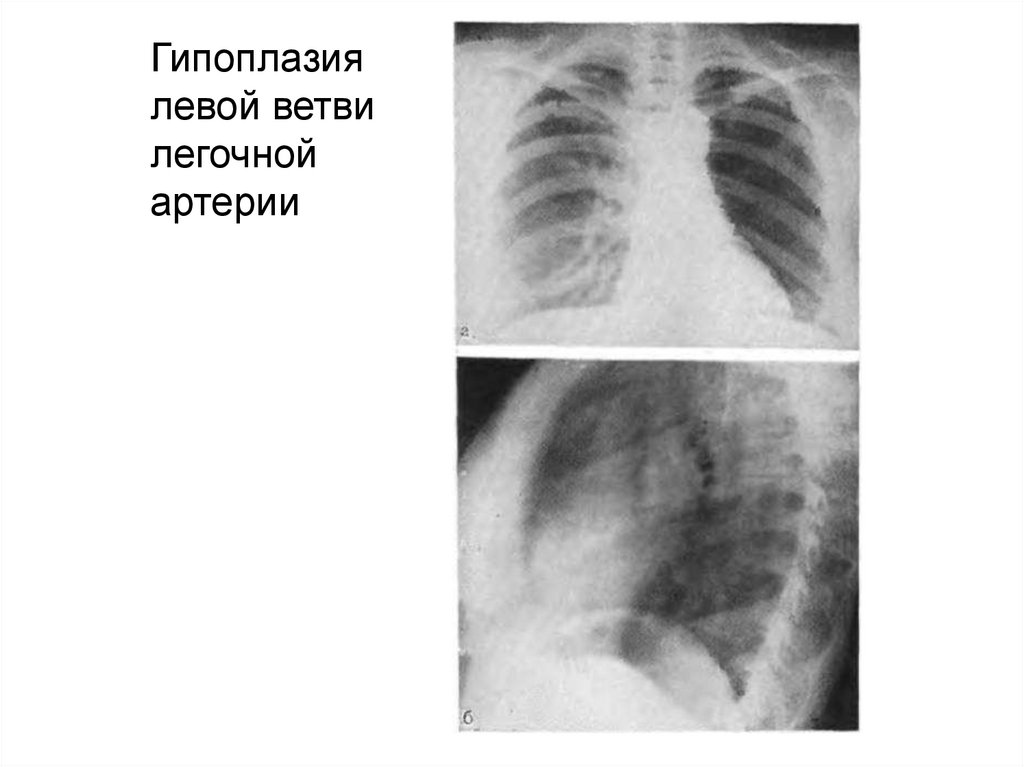

14.

Гипоплазия

левой ветви

легочной

артерии